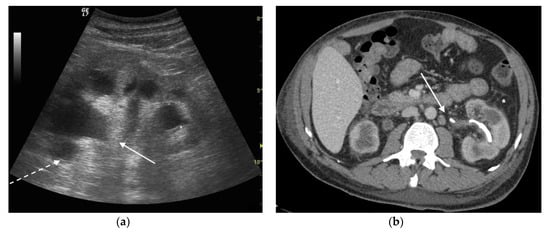

3. Ultrasound

4. CT